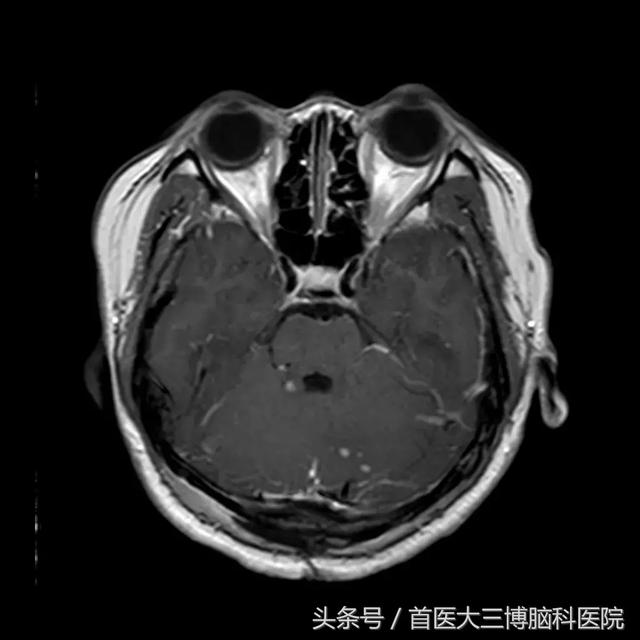

choroidfissurecyst脉络膜裂囊肿是见于脉络膜裂缝区域的良性颅内囊肿

形态较规则,没有骨板骨质破坏和周围脑组织的侵润表现,考虑良性病变